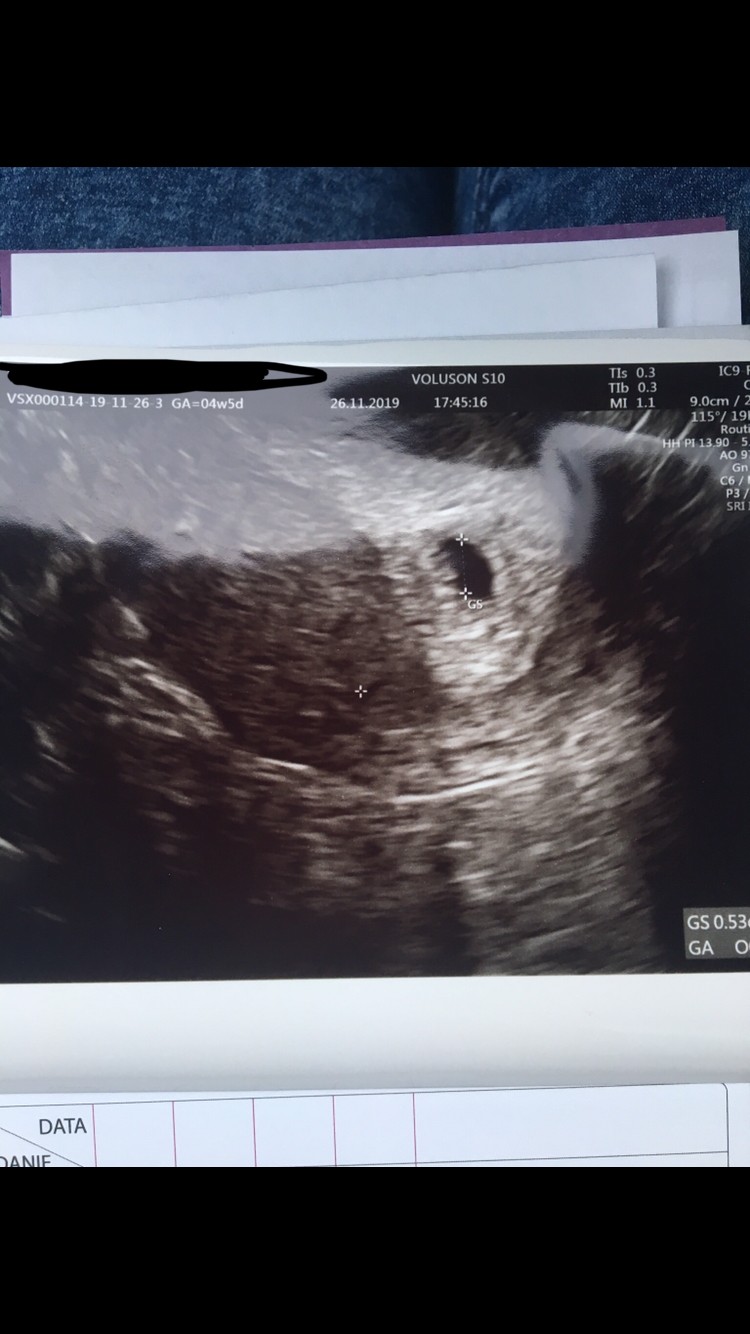

Czy to ciąża?

Załączniki

• CAF5DD56-6DC3-4E97-99EA-6740BEE3F09D.jpeg

CAF5DD56-6DC3-4E97-99EA-6740BEE3F09D.jpeg

127,3 KB · Wyświetleń: 138

No wczoraj już zobaczył ale malutki strasznie. Martwię się tylko bo lekarze nic nie robią z ta moja torbielą ona rośnie i mi dokucza boli często pulsuje aż do krzyża i naciska na pęcherz i moje samopoczucie jest średnie ale jakoś muszę wytrzymać jeszcze tydzień aż się okaże co i jak. W miejscu gdzie mam pęcherzyk ciążowy tez czuje lekkie pieczenie i ciągniecie ale to podobno normalnie